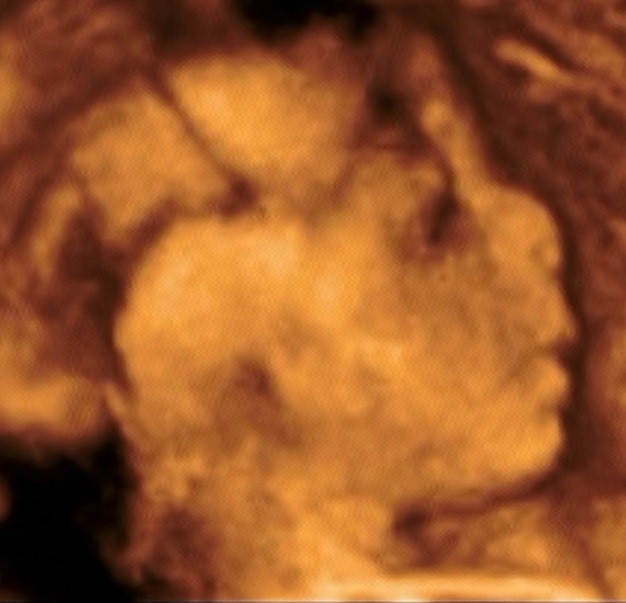

A teraz chciałam się pochwalić :)

Moja zdrowa, cudowna i upragniona Córeczka <3

• 4D (5).jpg

4D (5).jpg

85,8 KB · Wyświetleń: 88